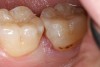

Replacement of existing restorations is responsible for 75% of all operative dentistry.15,19 The reasons for placement and replacement of restorations of direct restorative materials include: primary caries (Figure 1 and Figure 2); recurrent caries (Figure 3); poor margins (Figure 4 and Figure 5); restoration fracture (Figure 6 and Figure 7); tooth fracture (Figure 8); esthetics (Figure 9); non-carious tooth structure lost (attrition, abrasion, abfraction, erosion) (Figure 10); and pain/sensitivity.

Fig. 1 Initial caries. Class V carious lesions.

Figure 1  Initial caries. Class V carious lesions.

Figure 1